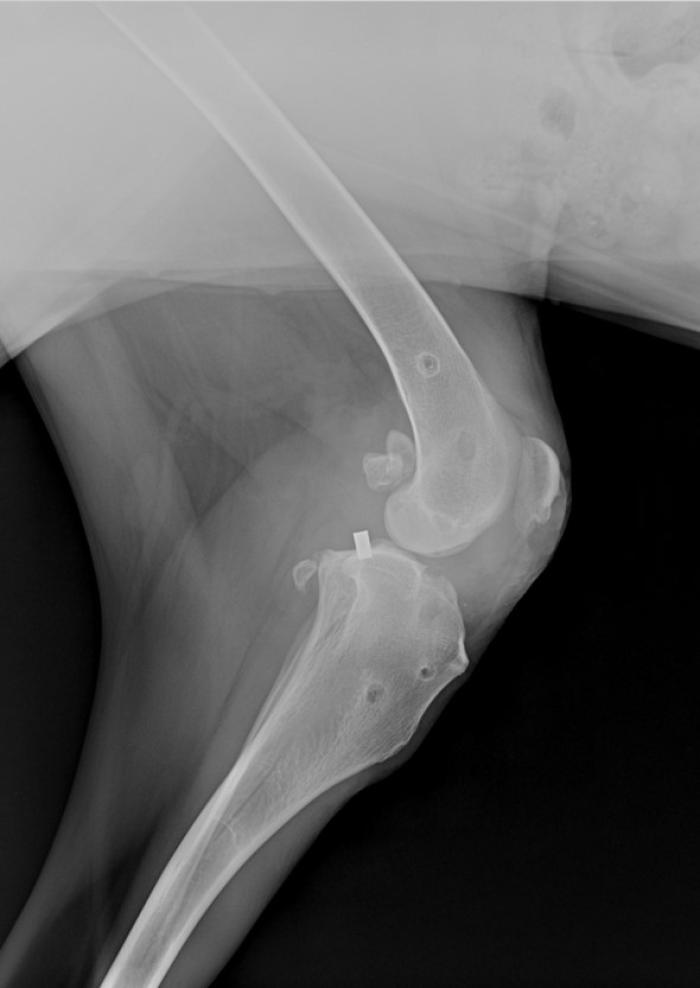

El ligamento de polietileno ultrarresistente de ultra alto peso molecular, se fija mediante tornillos interferenciales de titanio (Figura 2).

- la isometría: colocación de los puntos isométricos,

- las fibras libres: posicionamiento de las fibras libres (Figura 3),

- la tensión a ejercer: regular la tensión que ejerce ese ligamento.